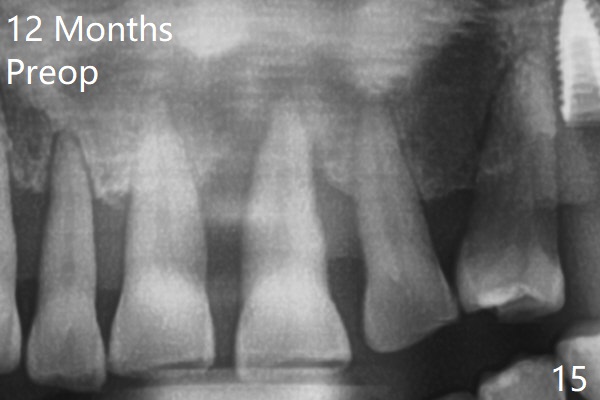

A 67-year-old man requests extraction of the loose tooth #9 (Fig.1). After extraction, the labial plate is found to be missing. With incision, allograft is kept in place with a 12x24 mm anterior narrow Cytoplast and 4-0 Chromic gut suture (Fig.2). Periodontal dressing dislodges in 2 days. The wound dehisces transversely 5 days postop (Fig.3 arrows), whereas the wound was open buccopalatal when the sutures were placed. Probably due to extensive dissection, the erythematous mucosa is large (Fig.4), although asymptomatic. When X-ray shows V-shaped bony defect (Fig.1 (PA), 5 (Pan), 6 (CT)), do not dissect the overlying thin buccal gingiva, which is most likely to dehisce. In fact immediate implant with guide appears to be more conservative, since there is no pressure against the buccal gingiva (Fig.7,8). To be more ideally, the implant could be placed more coronally, longer (13 mm instead of 11.5, Fig.9,10) and narrower (3.5 mm instead of 4.0 mm, Fig.11 (red circles: bone graft)).